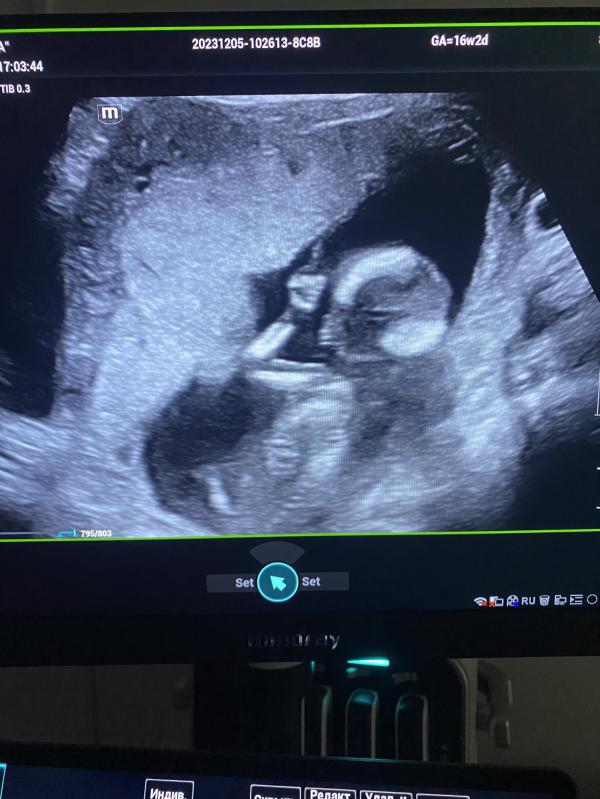

Почему приостановили выплаты по беременности? Отсутствие данных о посещении врача - что делать?

Остановили выплаты.

Из-за отсутствия данных о регулярных посещениях беременной врача женской консультации.